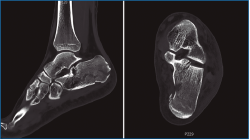

En las fracturas de calcáneo donde se afecta la articulación subastragalina posterior existe un trazo de fractura principal que separa 2 grandes fragmentos: el anteromedial “fijo” y el posterolateral, que se desplaza. Un segundo trazo de fractura ocasiona el hundimiento y la apertura de la subastragalina posterior. Sanders realizó una clasificación de estas lesiones intraarticulares basándose en la conminución y en las imágenes de tomografía computarizada (TC)(1).

Primero, realizamos limpieza de tejidos blandos y localizamos el flexor hallucis longus (FHL), que será el límite medial de seguridad. Recordamos que, en las fracturas de grado II de Sanders (Figuras 1 y 2), permanece íntegro un gran fragmento anteromedial, mientras que el fragmento posterolateral se desplaza. Tras la limpieza, identificamos la fractura (Figura 3) y movilizamos el fragmento lateral. Luego cambiamos los portales e introducimos el artroscopio por el portal medial, que nos permite acceder hasta el seno del tarso y visualizar el ligamento interóseo talocalcáneo. A través de un pequeño abordaje en la cara lateral del calcáneo reducimos la articulación subastragalina posterior (Figura 4A).

Figura 1. Fractura del calcáneo Sanders IIA.

Figura 2. Fractura del calcáneo Sanders IIB.